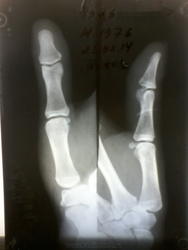

Прищемила палец дверцей машины, внешне изменения не выражены, только болит - есть перелом?

Обратила внимание на это образование. У Кролюка оно именуется "сверхкомплектная os hamulare terminale". А больше ничего не заметила.

Мне наоборот, кажется, что есть продольный перелом ногтевой фаланги. Качество не очень, поэтому на точность не претендую.

Видимо, Вы это просветление имели ввиду? Сомнительно. Контур гладкий. Послушаем, что скажет большинство.

+1. Стало много машин... и много сломаных концевых фаланг у дам ( подобное было недавно, но более демостративно, в силу того , что качество снимка было лучше).

Добавлю тогда свой взгляд и я.)

Поперечный надлом (неполный такой перелом) лучевого края основания ногтевой фаланги. И пусть боги с таким качеством опровергают и низвергают меня!)) Я - Никто, мне можно, простительно!))

+yesПо Muller - частичный суставной.

Есть ещё чёткость и гладкость контуров, если это добавочная кость. Или, напротив - неровность и нечёткость контура при переломе. Как правило, костный фрагмент имеет "гнездо", откуда он отошёл. На мониторе таких тонкостей мне не увидеть, Вам в натуре проще.

Спасибо всем за мнения, сама н\ф по снимку норма. Написала краевой основания, посчитала, что оторвался из участка просветления в основании н\ф. А атласа под рукой не было. Мне важно попадание в "десятку", так что совет из поста № 7 не очень подходит. Теперь уже что сделано, то сделано.

А лучевой контур фаланги Вас совсем не напугал, да?.. Надеюсь, на контроле он не изменит своего поведения.